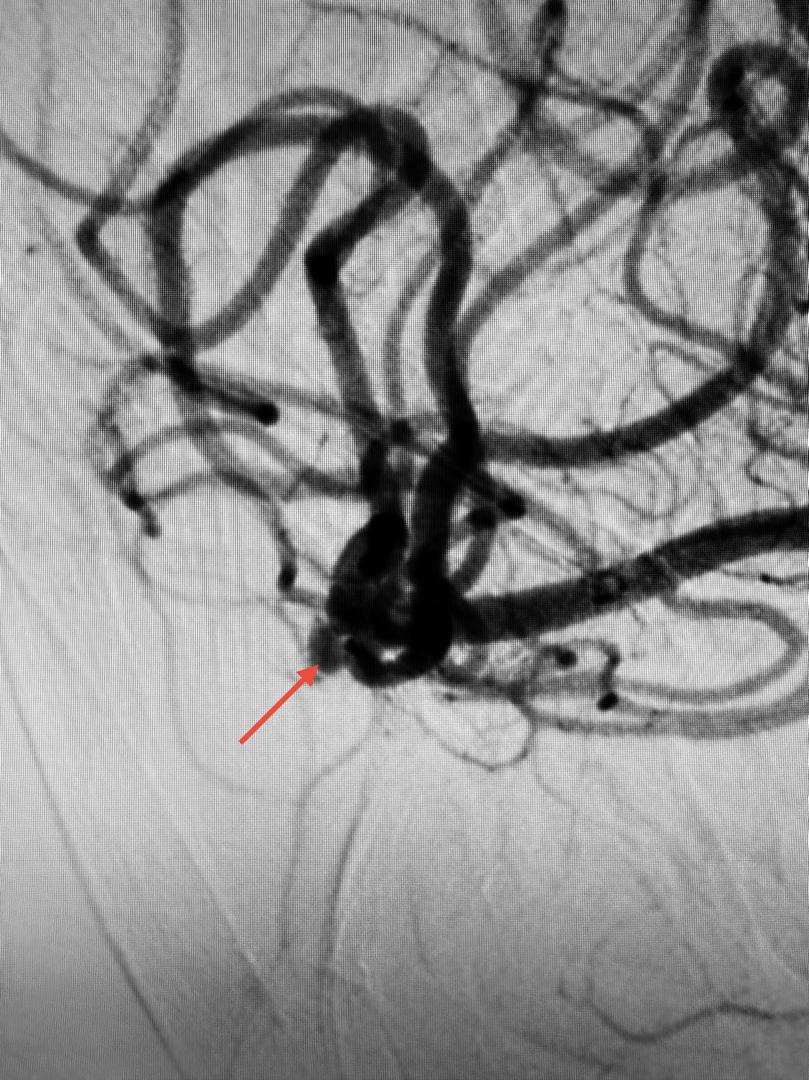

At PCSH, a Digital Subtraction Angiogram (DSA) confirmed the aneurysm’s presence.

“Using a 1.7F microcatheter (with a diameter smaller than 1mm), the team carefully delivered a platinum coil 2mm in diameter and 4cm in length into the aneurysm sac.

“The coil was electrically detached once securely positioned, filling the aneurysm and preventing any further blood flow into it.

“Only the coil remains in the aneurysm, effectively neutralizing the risk of rupture,”